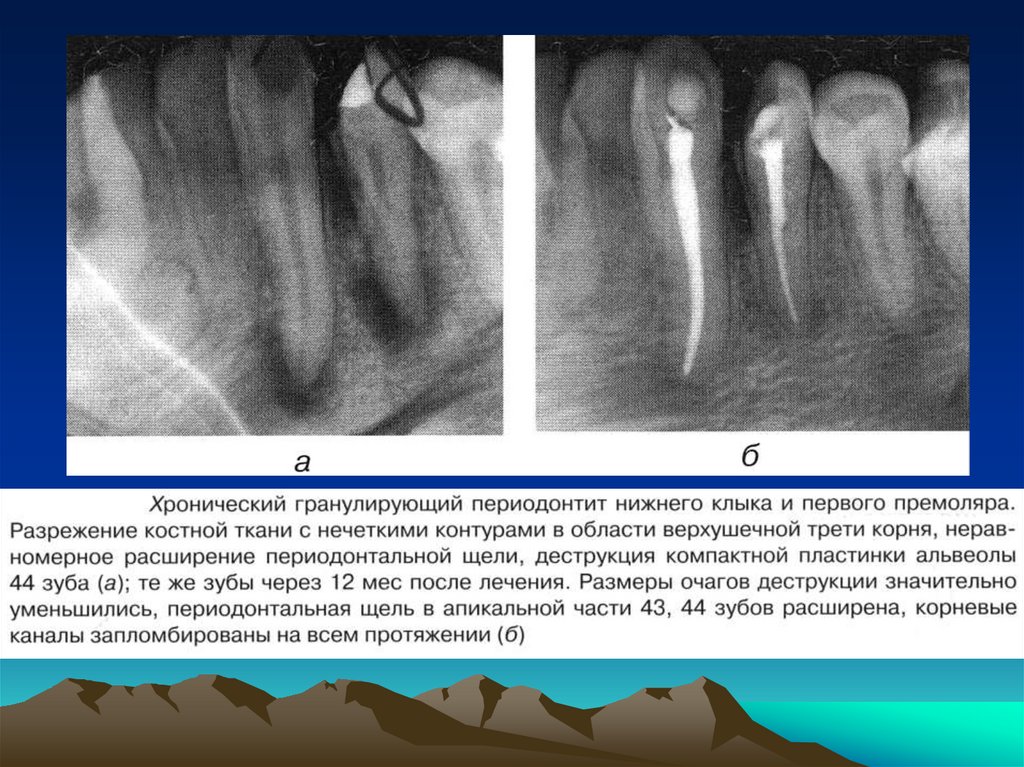

соматического

и